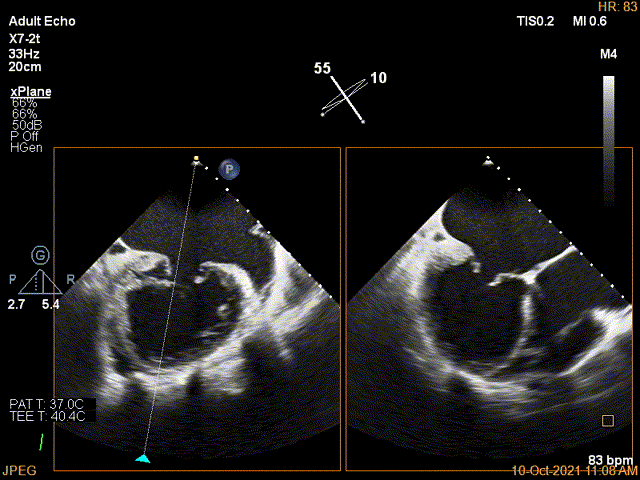

3D确认左房较大,穿刺点位近似于3点位

3D视图下大鞘位置及长度测量

2D视图下trajactiory

X-plane:下夹子尝试先捕获1区脱垂瓣叶